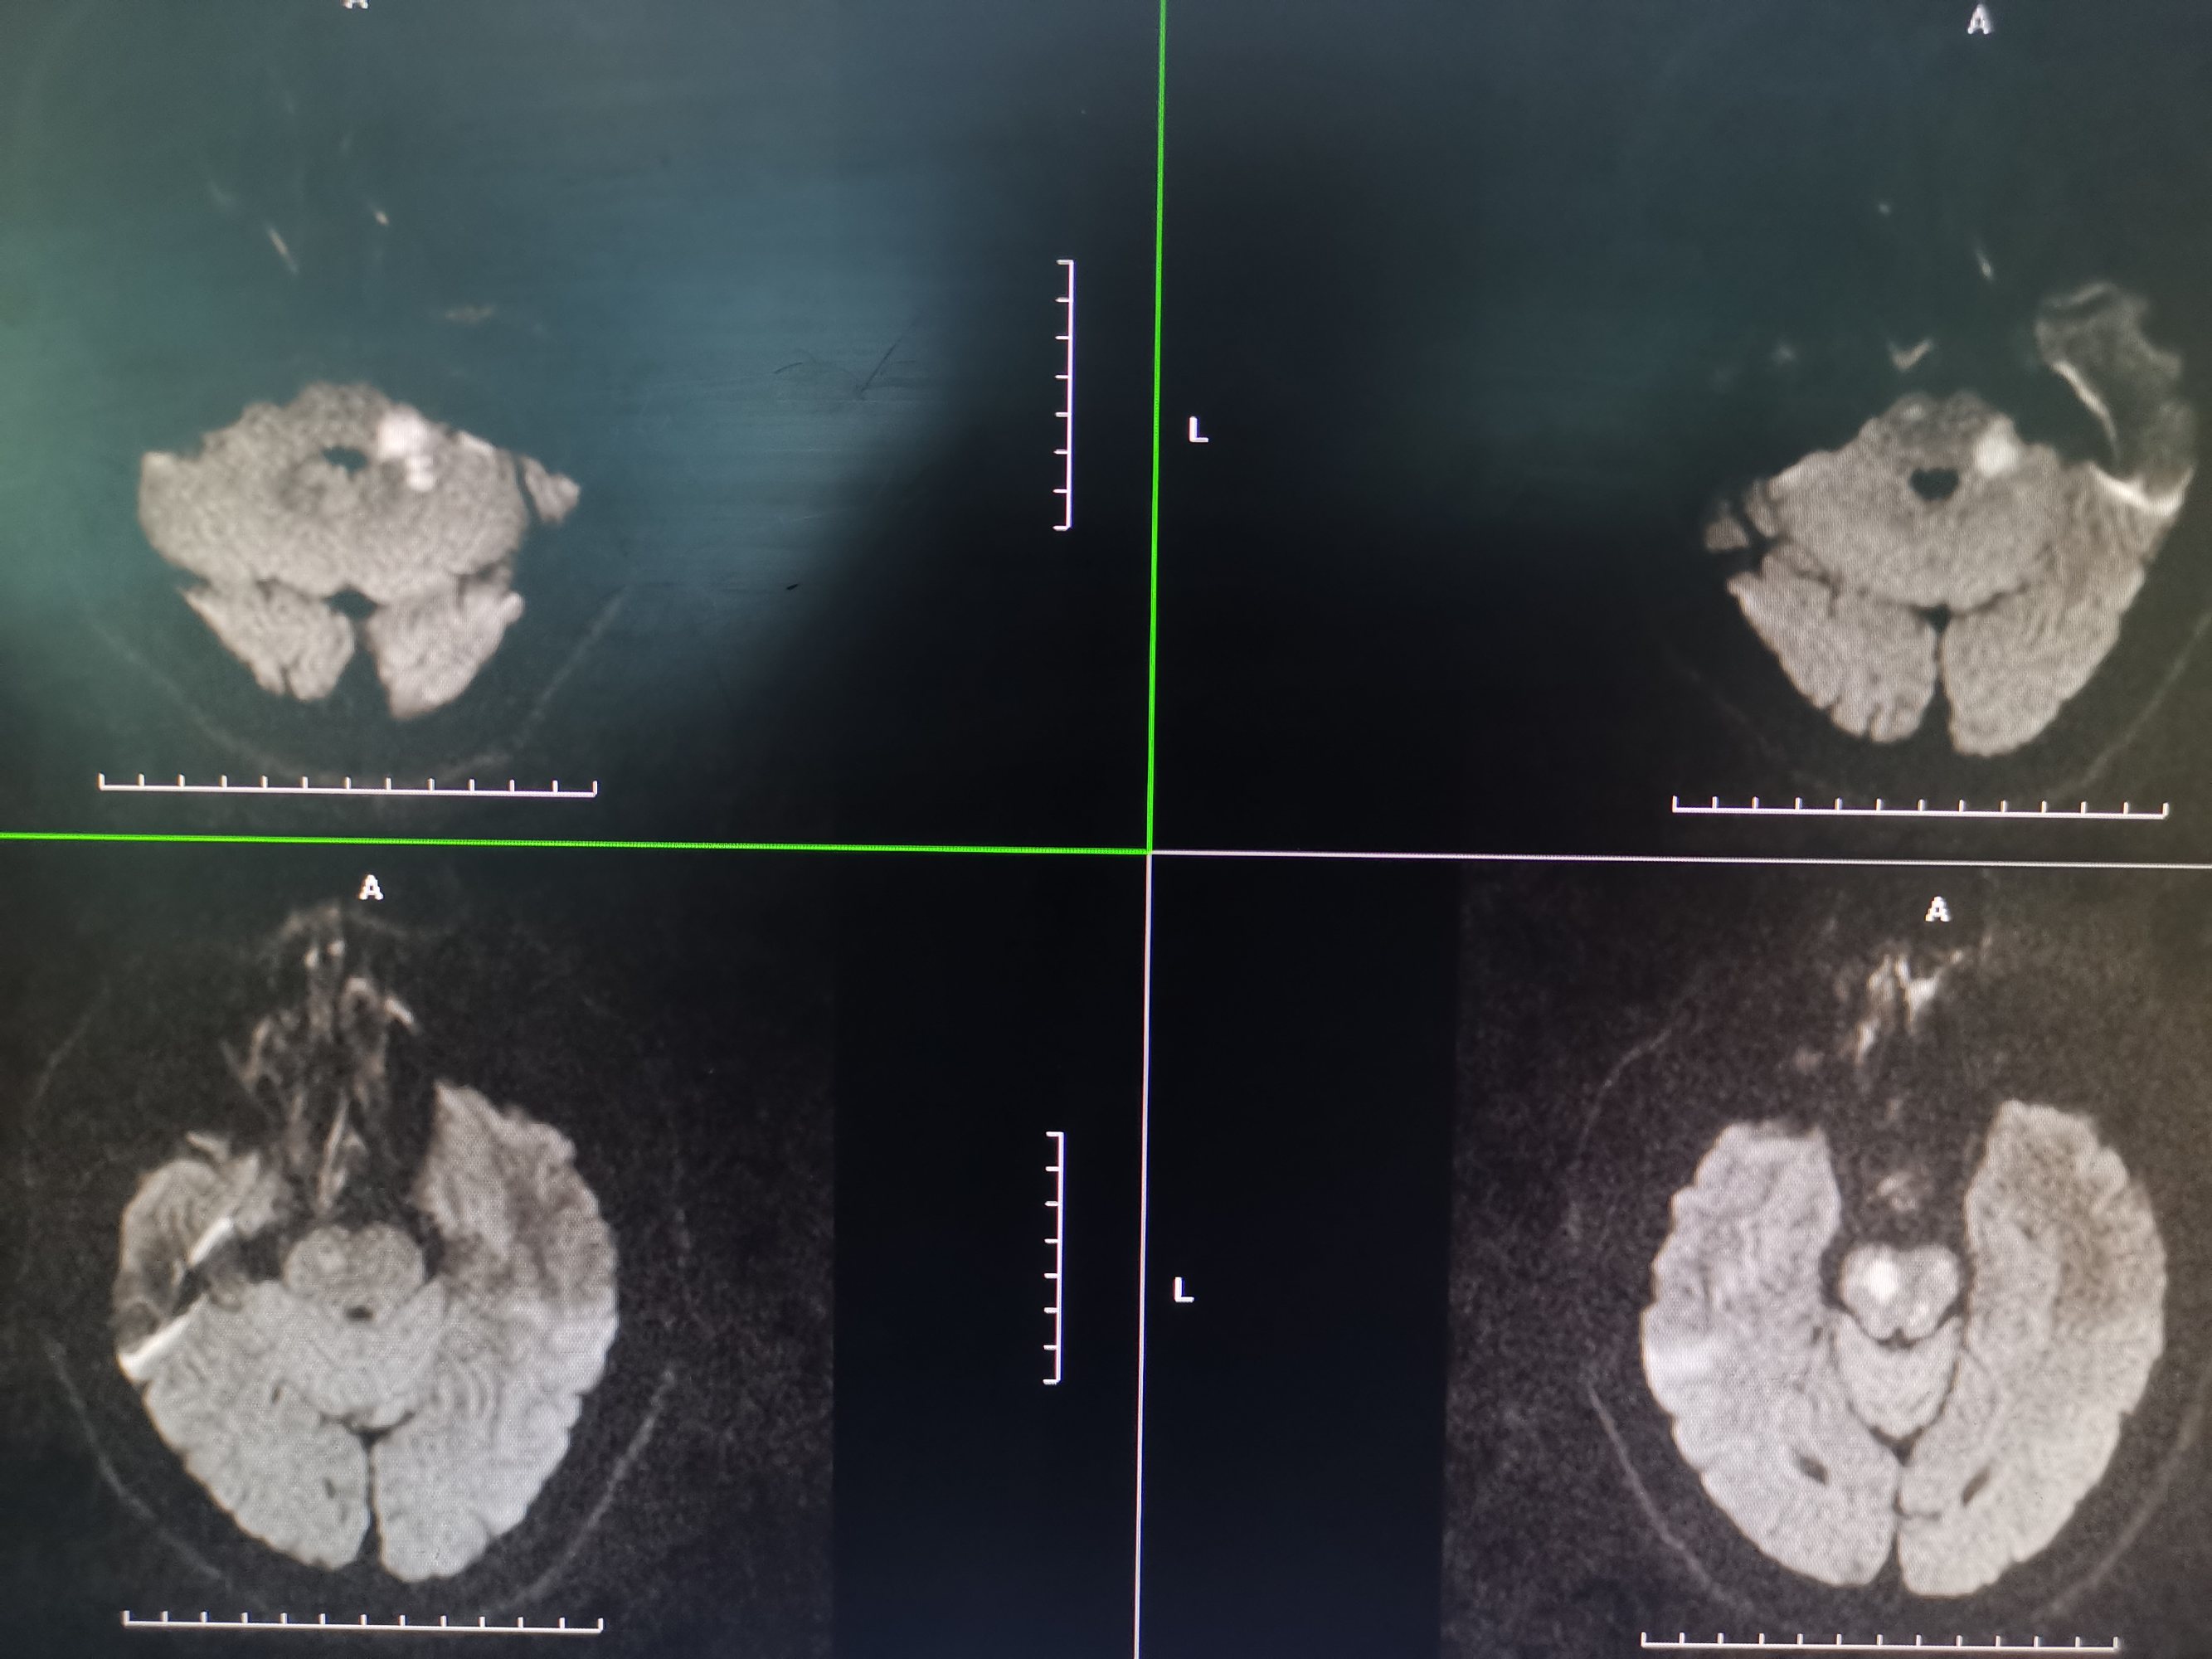

入院MR